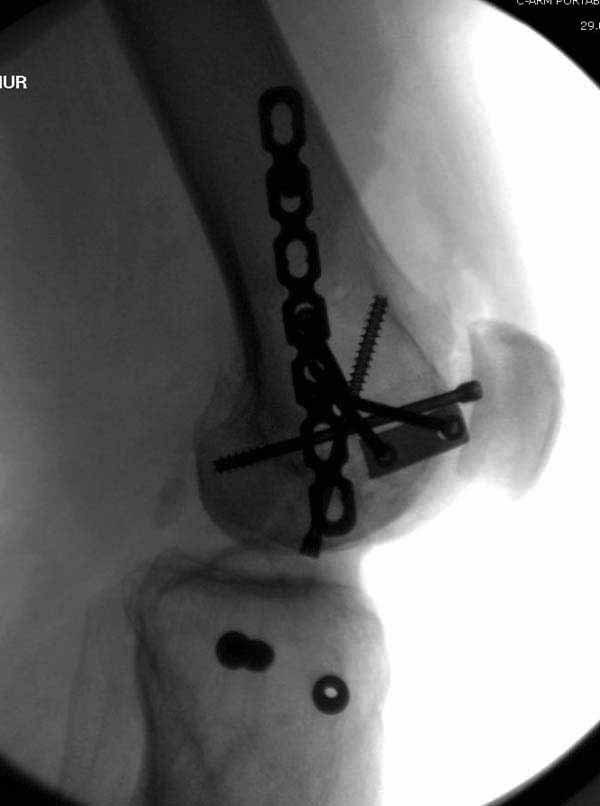

Ответ на эту часть Вашего поста – вложенный файл. Больная оперирована неделю назад по поводу открытого перелома дистального эпиметафиза бедренной кости. После операции она идёт в рентгенкабинет для выполнения послеоперационной контрольной рентгенографии, представленной на слайдах 10 и 11. Узнав, почему её фотографируют, просила передать Вам, Антон, привет.

В приложении пример недавней операции, C3, открытая репозиция, фиксация мыщелков спицами и винтами, ретроградный синтез большеберцовым гвоздем 10,5 мм диаметром, винты 5 мм.